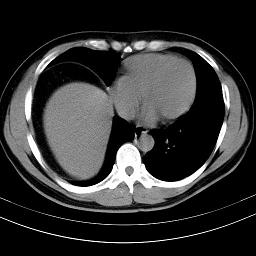

标题: CT18388:肝脏膈肌间隙内大量脂肪密度影 [打印本页]

标题: CT18388:肝脏膈肌间隙内大量脂肪密度影

考虑----气腹可能性大---进一步检查

是脂肪不是气体,有时候会碰到这样的病人,脂肪过多吧。

腹腔脂肪沉积过多

局部脂肪沉积。

膈下脂肪沉积。

考虑膈下脂肪沉积。

腹腔脂肪沉积症

激素治疗的病人容易脂肪沉积